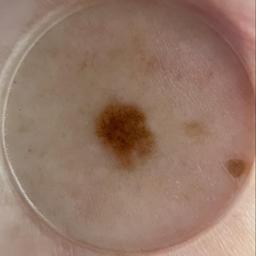

ISIC_4008974

acquisition_day 285

age_approx 60

anatom_site_1 Trunk

anatom_site_2 Anterior trunk

anatom_site_general anterior torso

concomitant_biopsy False

diagnosis_1 Benign

diagnosis_confirm_type single image expert consensus

family_hx_mm True

image_type dermoscopic

personal_hx_mm True

sex female